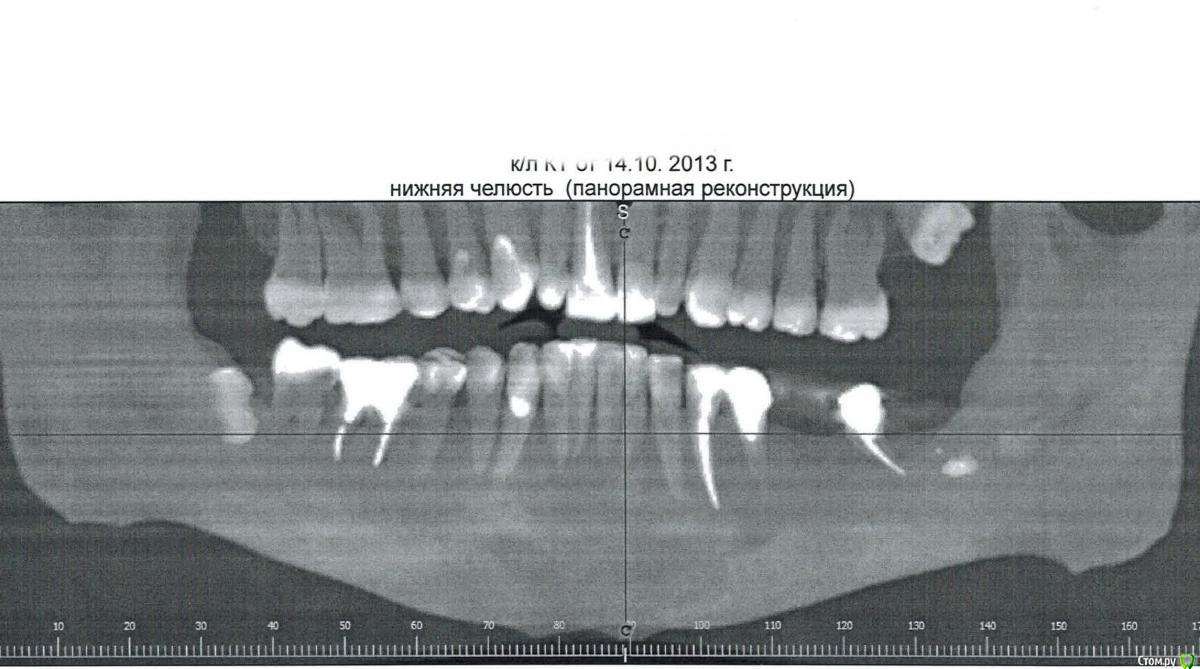

patient2015 Опубликовано 2 октября, 2015 Поделиться Опубликовано 2 октября, 2015 Здравствуйте, посоветуйте наилучшую систему для имплантации 46 зуба по соотношению цена-качество. Переплачивать за навороты не хочется, но у меня аутоиммунное заболевание, поэтому нужен чистейший титан, чтобы прижилось на 100%. Врач ставит помимо Nobel и Replace запатентованные собственные импланты, какие могут быть риски? Сказал подойти через 2 месяца после удаления, действительно кость так быстро нарастет и не потребуется синус-лифтинг? http://s017.radikal.ru/i401/1510/19/68bf52ca58ae.jpg Ссылка на комментарий